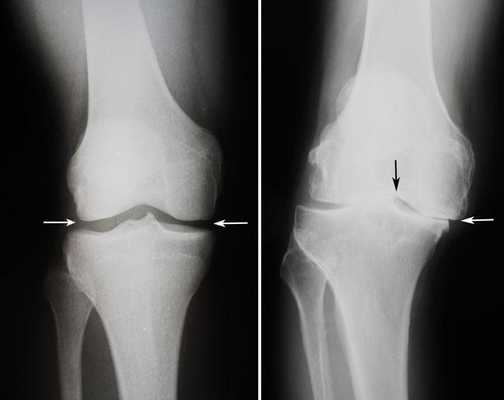

Посмотрите на рентген, на нем вы видите, до какой степени при запущенном гонартрозе изношен гиалиновый хрящ, обеспечивающий гладкое скольжение суставных поверхностей. Концевые участки костей грубо деформируются нарушая функции сгибания и разгибания конечности вызывая интенсивный болевой синдром.

Динамика болезни на рентгене.

Откладывать хирургию при гонартрозах 3-4 степени чревато деформацией позвоночника. Это происходит из-за хромоты. Дегенеративные процессы артроза глубоко затронут кости, из-за чего они приобретут хрупкость, потеряют плотность и зафиксировать к ним компоненты импланта станет сложно.